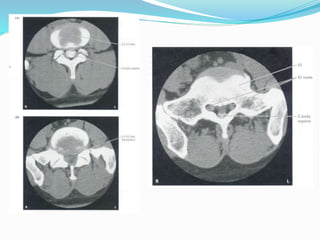

RAIZES NERVOSAS X VERTÉBRAS, DISCOS E

LIGAMENTOS